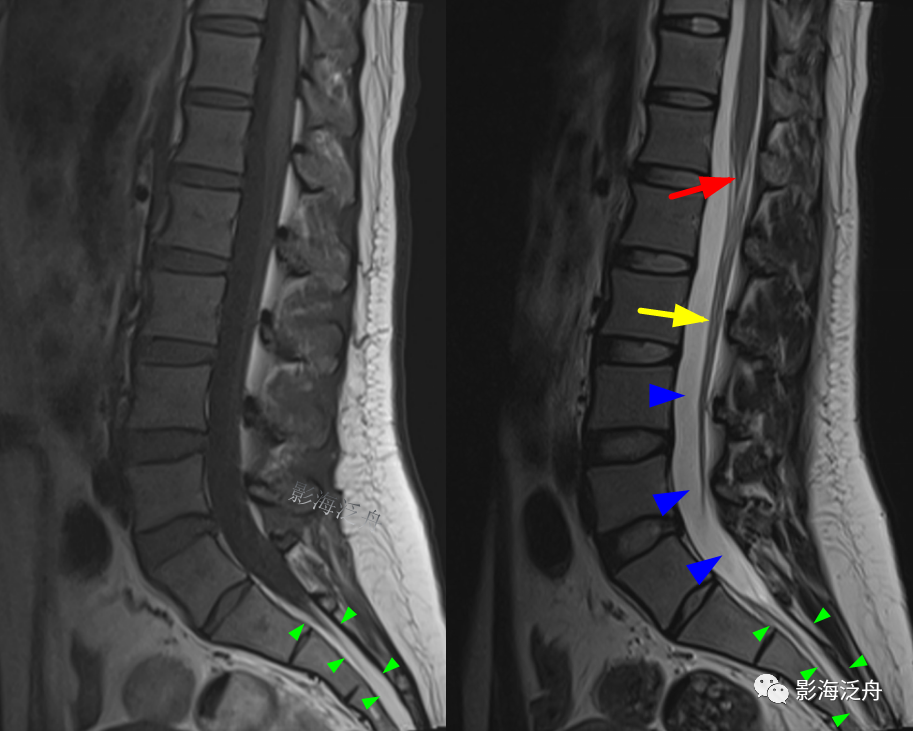

如果没看出来,我把两张图放一起

正常的腰骶部MR解剖:在脊髓圆锥(红箭)水平以下,椎管内走行的主要是终丝及马尾神经(黄箭),大量脑脊液填充在硬膜囊内(蓝箭头);硬膜囊以外的椎管内只有少量脂肪组织填充(绿箭头)。

为了方便大家记忆,笔者标注了一个腰椎矢状切面解剖标本,用来跟正常腰椎MR图像对照观察。